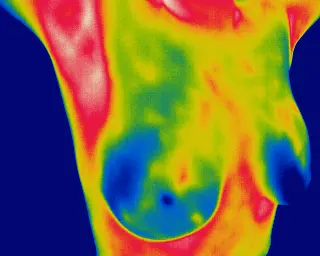

Deep Pain-Free Detection

Thermography detects the vascular changes in the blood vessels that are going to feed an early tumour, between 6 -10 years earlier than you would notice on a mammogram.

It's important to let your clinician know if you have anxiety or fear of the scan. They can work with you to help make your visit more comfortable. It is also important to know that during the vidit, the clinician, or the Thermocheck  do not touch your breast, and no radations are emitted, it is a Thermographic camera technology, so it is exactly like taking a picture with your camera at about 50 cm of your breast. That is it.